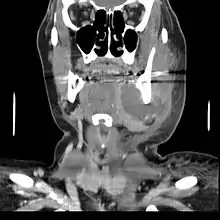

| A decayed, broken down tooth, which has undergone pulpal necrosis. A periapical abscess (i.e. around the apex of the tooth root) has then formed and pus is draining into the mouth via an intraoral sinus (gumboil). | |